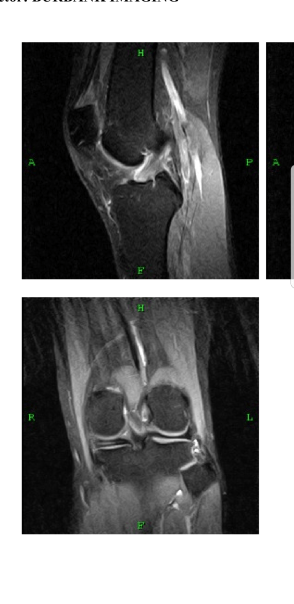

Here you can see the right side (your left) with a layer of cushioning (the meniscus) between the tibial head and the femoral head. On the other side, it’s missing. I found out just the other day that I have torn my medial meniscus and after scouring books, emailing doctors and reading up on the subject, there are 3 possible roads ahead. 1: I recover naturally with minimum risk of osteoarthritis due to the rubbing of the tibia and femur. This takes 6 to 8 weeks of limited activity such as swimming and bicycling without any pain. If there’s pain, I stop. 2: The pain escalates, and I go in for surgery (a last resort). The surgeon does one of two things based off what he notices during the arthroscopy (a process whereby the doctor places a scope bilaterally into the knee to get a clear view of what’s going on). 3: I never do rigorous exercise again and just live with it.